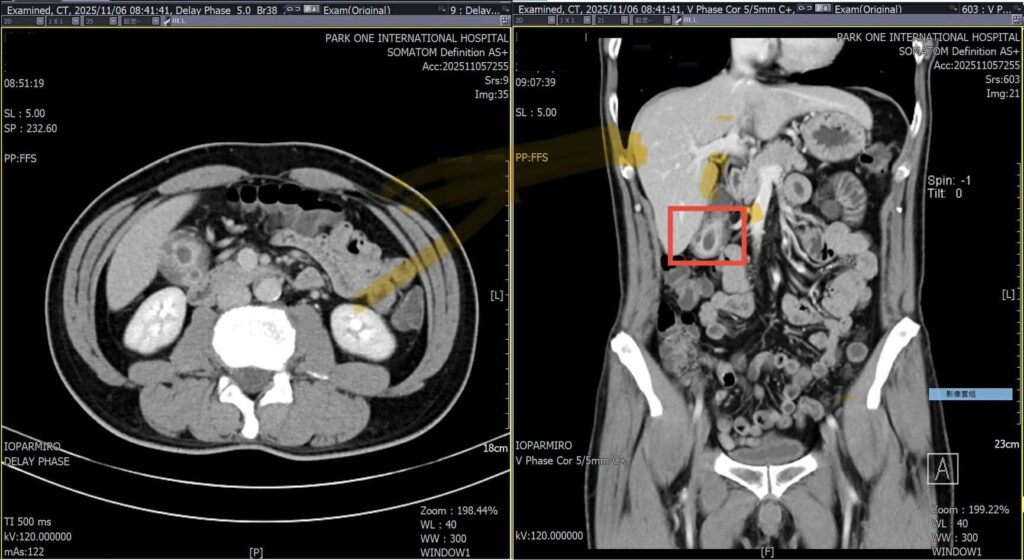

圖2說:博田國際醫院電腦斷層掃描發現,男子的膽囊壁竟異常廣泛性增厚達正常的六倍,確認為臨床上常與膽結石混淆的「膽囊腺肌症」。(博田國際醫院)

【記者廖銘瑞/高雄報導】49歲的林姓男子五年來,因心窩悶痛與右上腹脹痛四處求醫,做過胃鏡與多次超音波,皆僅顯示輕微胃炎或無結石異常,反覆發作的疼痛成了長期困擾,卻始終找不到病因,近期至博田國際醫院肝膽胰外科看診並接受檢查時,才被發現膽囊壁竟異常廣泛性增厚達正常的六倍,進一步電腦斷層掃描終於確認,是臨床上常與膽結石混淆的「膽囊腺肌症」。

膽囊腺肌症的影像表現其實分成不同型態:有些病灶只侷限於膽囊底部,屬於「局部型」,常在其他檢查中偶然被發現;另一類則出現在膽囊體部,形成明顯的壁層收縮,稱為「節段型」,此型態因與文獻中較高的膽囊癌風險相關,在臨床上特別受到重視;還有一部分患者屬於「廣泛型」,整個膽囊壁都呈現全面性肥厚,容易掩蓋早期惡性變化,使影像判讀更加複雜。正因為三種類型的分佈部位不同、臨床意義也不同,影像醫學的細膩觀察成了確診關鍵。